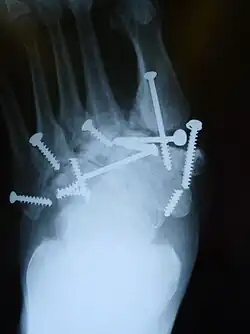

- Mit Metall-Schrauben die gebrochenen Knochen und Gelenke stabil zu verbinden, kann die Gelenkverknöcherung fördern, die normalen Gelenk-Strukturen und Funktionen aber nicht wieder herstellen. Wird ein derart verschraubter Fuß ungeschützt zum Gehen benutzt, brechen die Schrauben oft[20] (Ermüdungsbruch), was anzeigt, welch starke Biege-Kräfte bei jedem Schritt repetitiv auf das Fußskelett einwirken.